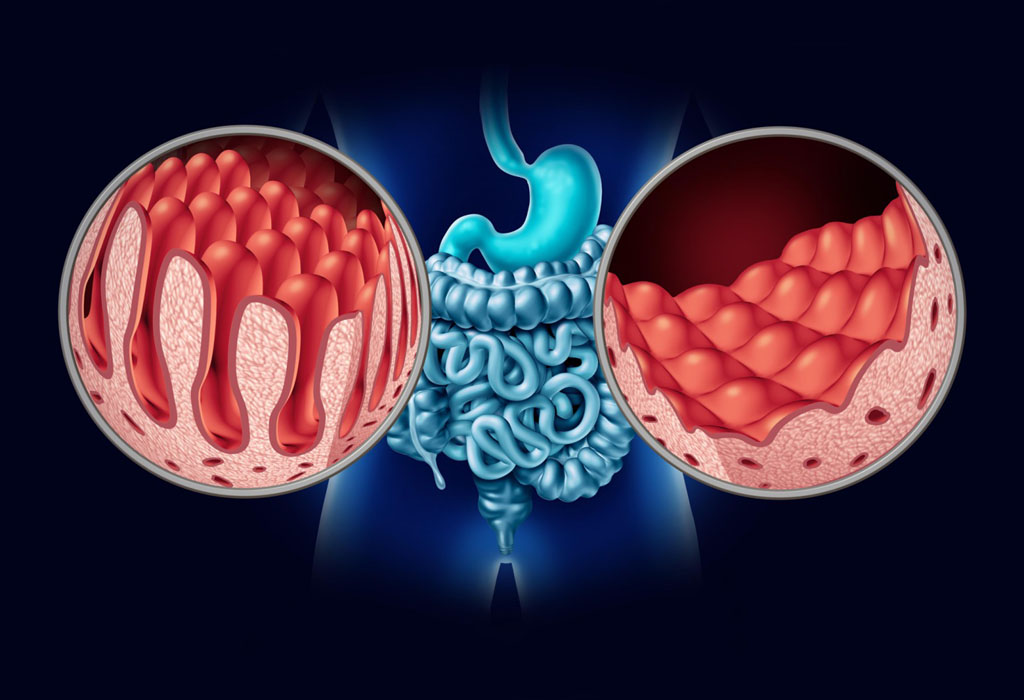

Ukoliko početno mjerenje pokazuje visoke vrijednosti krvnog tlaka, mjerenje treba ponoviti isti dan, a zatim dvaput dnevno u naredna dva dana kako bi se sigurno utvrdilo da je krvni tlak trajno povišen. Nakon postavljanja dijagnoze povišenog krvnog tlaka potrebno je odrediti i učinak povišenog krvnog tlaka na važne organe: posebno na krvne žile, srce, mozak i bubrege. Postoji opravdano mišljenje da su promjene na mrežnici slične promjenama na krvnim žilama bilo gdje u tijelu, na primjer u bubrezima.

Diuretici pomažu bubrezima da uklone sol i vodu čime smanjuju volumen tekućine u tijelu i tako snizuju krvni tlak. Diuretici također izazivaju i širenje krvnih žila. Budući da kako najbrze sniziti krvni pritisak dovode do gubitka kalija mokraćom, ponekad uz diuretike treba uzimati preparate za nadoknadu kalija ili lijekove koji čuvaju kalij u tijelu sprječavaju njegovo izlučivanje mokraćom.

Liječenje bubrežne bolesti može, katkada, normalizirati krvni tlak, ili barem ga tako sniziti da antihipertenzivna terapija bude učinkovitija. Suženje stenoza bubrežne arterije može se otkloniti uvođenjem katetera s balonom koji se u bubrežnoj arteriji napuše i raširi suženu arteriju.